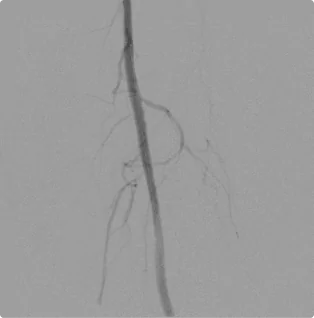

Female – Age 77

Referred by her Podiatrist for Severe Gangrene of the Left Foot

This patient’s left foot was at critical risk for needing amputation or major bypass surgery. She had a “total chronic occlusion” in the main artery in her thigh, almost entirely cutting off blood flow down the leg. With no strong arteries flowing in her leg, blood was forced into tiny side vessels, which could not supply the required amount of blood to the limb. Using cutting-edge endovascular techniques, Dr. Goldstein worked from both on top (downwards) and below (upwards) the blockage to open the artery with atherectomy, angioplasty, and stenting. When most doctors would have given up, Dr. Goldstein’s persistence allowed for the preservation of her foot. The team at Pedes Orange County closely monitors the arterial flow in her leg to intervene when it begins to close again.

Before

Before the intervention, blood flows backward and around through small side vessels to bring blood down the foot.

After

After the intervention, there is an efficient pathway for blood to move to the foot and revive the tissue.